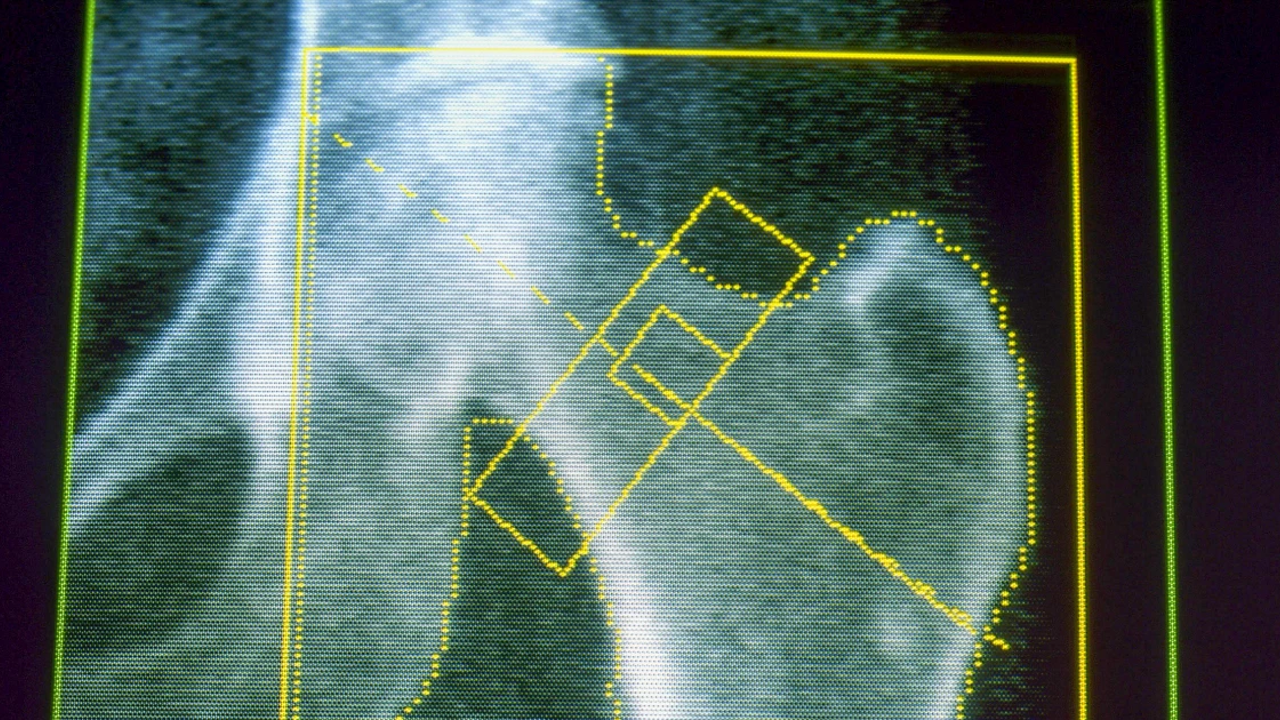

GLP-1 drugs, including Ozempic and Wegovy, may be linked to a slightly higher risk of osteoporosis and gout, according to research presented at the American Academy of Orthopaedic Surgeons' annual meeting. The study, led by Dr. John Horneff from the University of Pennsylvania, examined five years of medical records from over 146,000 adults with a diagnosis of obesity and Type 2 diabetes for their risk of these conditions. It found that about 4% of GLP-One users developed osteopOrosis, compared to 3% of non-users, and rates of gout were also slightly higher. The research, which was observational, could not prove that the medications caused either condition. However, it is unclear if rapid weight loss or some other medical benefits with GLP1s can be attributed to the drug.